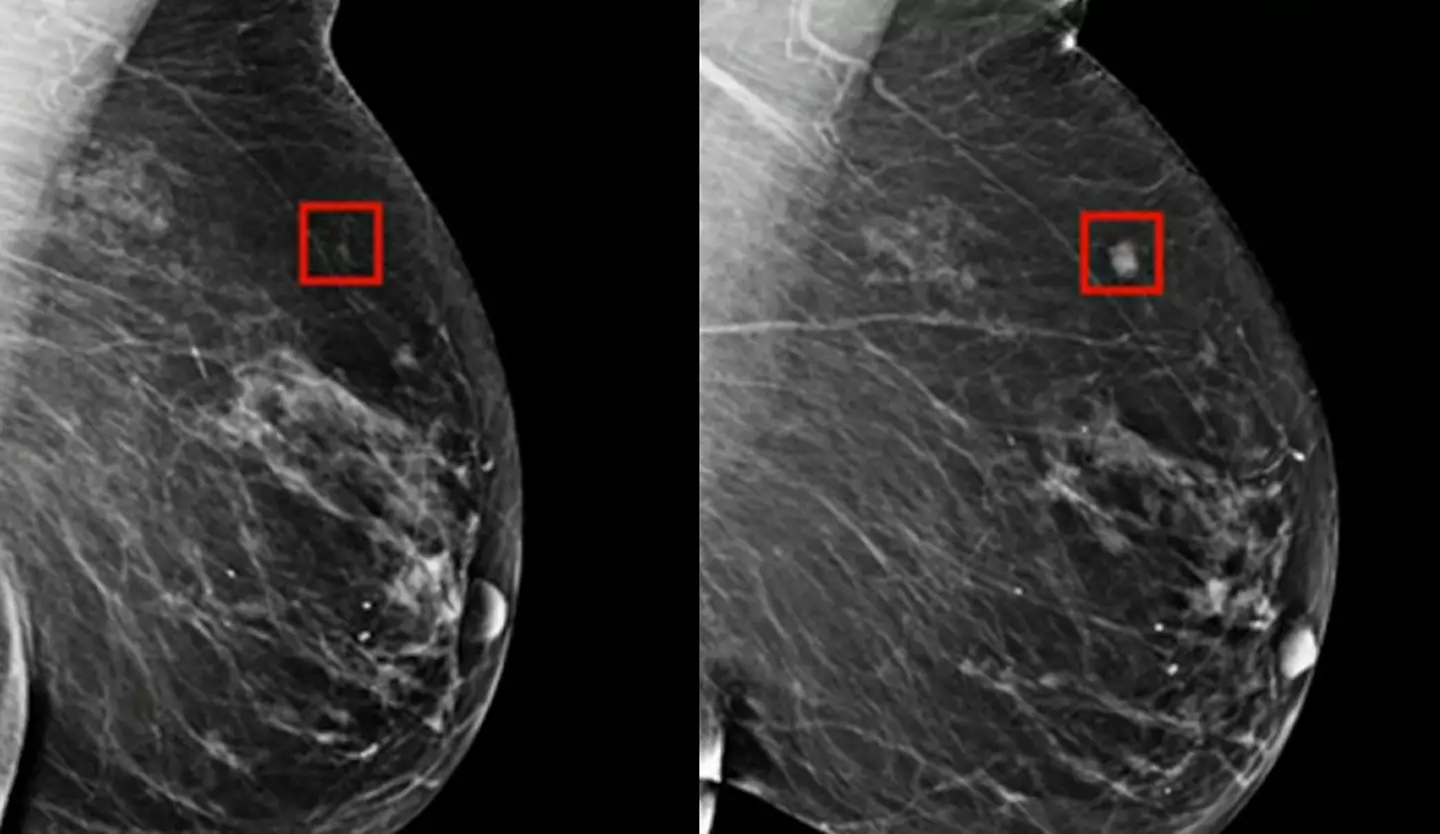

He said: "AI is a tool that machines use for looking at images and comparing those images to ones that have already been recorded in the machine to identify abnormalities.

"This technology can look at mammograms and identify areas that a human radiologist may want to look at more carefully.

According to the New York Times, the use of this AI technology in breast cancer screening has reduced the workload of a radiologist by around 30 percent while increasing cancer detection rates by 13 percent which sounds like entirely positive news.

They also report that the AI was tested with some of the most challenging cancer cases where the early signs of breast cancer had not been spotted by radiologists, with the AI successfully managing to identify the cancer.